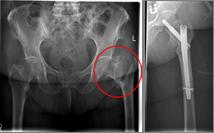

In older age and with stronger displacement of the fracture can be done by a duo-head prosthesis. Here only the femoral head is replaced, the hip socket is preserved. In case of simultaneous hip arthrosis, a total endoprosthesis (hip replacement) with replacement of the acetabular cup can be used.

Oberschenkel 3

Picture: This picture shows the treatment of a severely displaced fracture with a so-called duo head prosthesis. The acetabulum was left here.